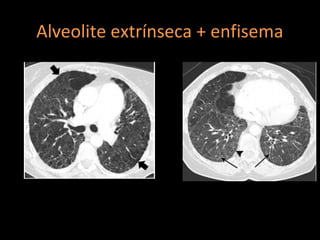

Alveolite extrínseca + enfisema

http://radiographics.rsna.org/content/30/7/1753.full.pdf+html